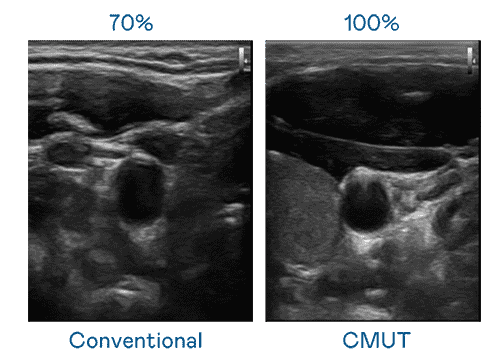

CMUT 技术是一种用电容式微机电元件来产生超音波讯号的技术。。。。与传统 PZT 压电式技术相比,,,CMUT 频宽增加 30%,,更宽频的超音波讯号让影像解析度大幅提升,,是实现高影像品质医疗超音波扫描、、、促进精准医疗发展的关键技术。。。

大频宽带来超清晰影像

超音波影像的解析度高低,,首先取决于探头能发出的讯号频宽。。。。尊时凯龙 CMUT 可提供高清晰的超音波讯号,,,提供高频宽、、、、高灵敏度、、、影像纹理细节更高的超音波影像,,,,协助医护人员缩短影像判读时间及利用精准的医疗影像进行诊断。。。。